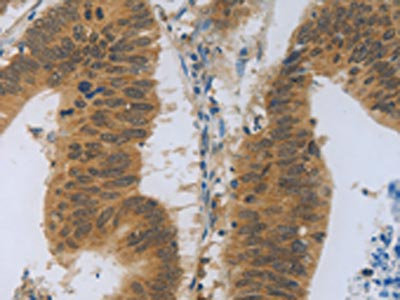

The image on the left is immunohistochemistry of paraffin-embedded Human colon cancer tissue using CSB-PA213664(TNFRSF11B Antibody) at dilution 1/30, on the right is treated with fusion protein. (Original magnification: ×200)

The image on the left is immunohistochemistry of paraffin-embedded Human breast cancer tissue using CSB-PA213664(TNFRSF11B Antibody) at dilution 1/30, on the right is treated with fusion protein. (Original magnification: ×200)